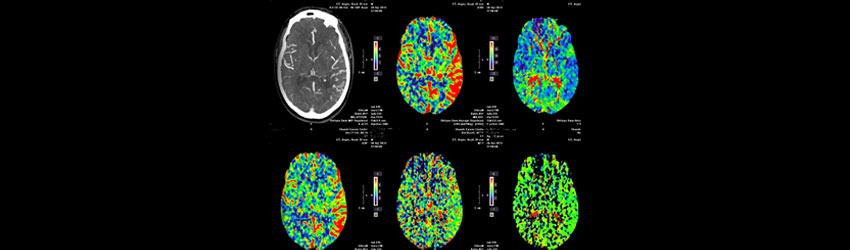

After initial neurological assessment, CT angiogram of the head and neck was obtained which demonstrated blockage of the main blood vessel supplying the left part of the brain

project image After administering thrombolysis (Clot buster medication), Neurointervention (Thrombectomy-Clot Removal via Catheter) was performed which restored the blood flow to the entire brain.